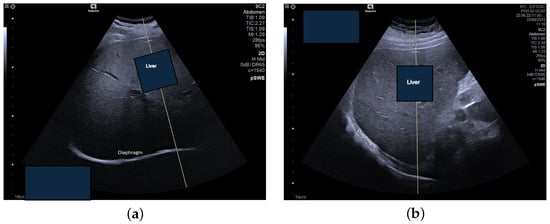

The second set of images acquired for this study is composed of 96 elastography images—61 of NAFLD patients and the remaining 35 of healthy subjects. These were obtained at the School of Health Technology from Coimbra, extracting data from 50 participants, ranging from 18 to 50 years old. A consistent procedure was used to acquire the images for the dataset. Each subject was studied by a single operator who performed fist the US assessment of the liver steatosis in B-mode. A portable ultrasound (Acuson P500) with a convex transducer (5.2 MHz), was operated by one experienced researcher (>20 years). The collection was conducted during rest. Shear-wave elastography (SWE) data collection was conducted using the abdomen shear module of an Acuson Sequoia Ultrasound System 2018; this device was coupled with a convex transducer (9C2 Mhz). Figure 2 and Figure 3 are examples of acquired images. In order to maintain consistency across all acquisitions, a quality factor of over 65 was consistently achieved, enhancing the accuracy of classification and analysis, as well as image quality. The settings were maintained at a frame rate of 27 fps (frames per second) and a vertical scale (V scale) of 95%.

Sensors 24 07568 g002

Figure 3. Intercostal scan of the right lobe of the liver, acquired with the Acuson Sequoia ultrasound system equipped with Auto pSWE and ultrasound-derived fat fraction (UDFF) technique. The inner rectangle is the fixed measurement box: (a) UDFF = 8% (no steatosis), (b) UDFF = 19% (steatosis).